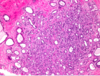

Q

A

BR; invasive ductal

BL: dcis

TR: invasive lobular

TL: insitu loblar